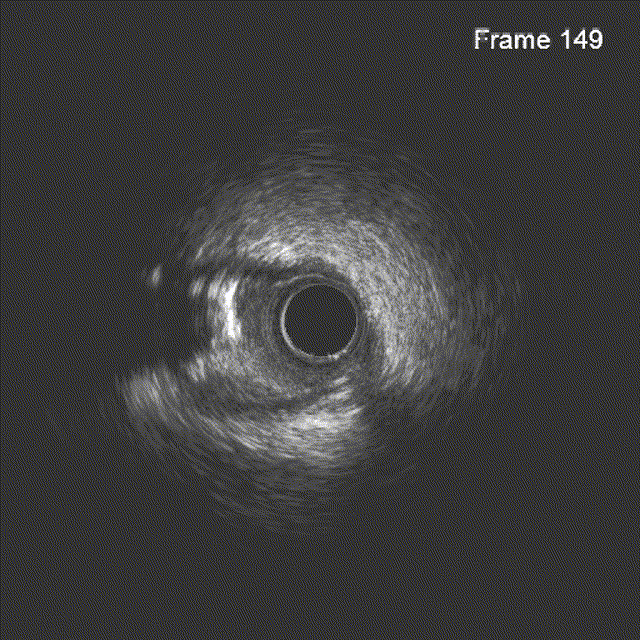

IVUS见左主干远段MLA:7.05mm²;前降支近段MLA:2.68mm²,中段MLA:2.63mm²,前降支近段至中段可见多发钙化小节突入管腔,局部90°-270°钙化,前降支开口至中段管腔直径约2.5-3.5mm,严重钙化段管腔直径约2.85-3.5mm。

根据IVUS结果,调整术式为精确定位前降支开口,预处理方式用3.0mm×12mm shockwave冠脉血管内冲击波导管。

冲击波导管送至左前降支,由中段至开口依次以4atm压力初始冲击扩张,6atm压力巩固扩张,共冲击扩张10秒×8个周期,可见球囊逐渐膨胀充分。此阶段在处理前降支开口时预置回旋支保护导丝。

复查IVUS提示前降支原近中段钙化斑块、钙化小节碎裂,未见明显夹层。